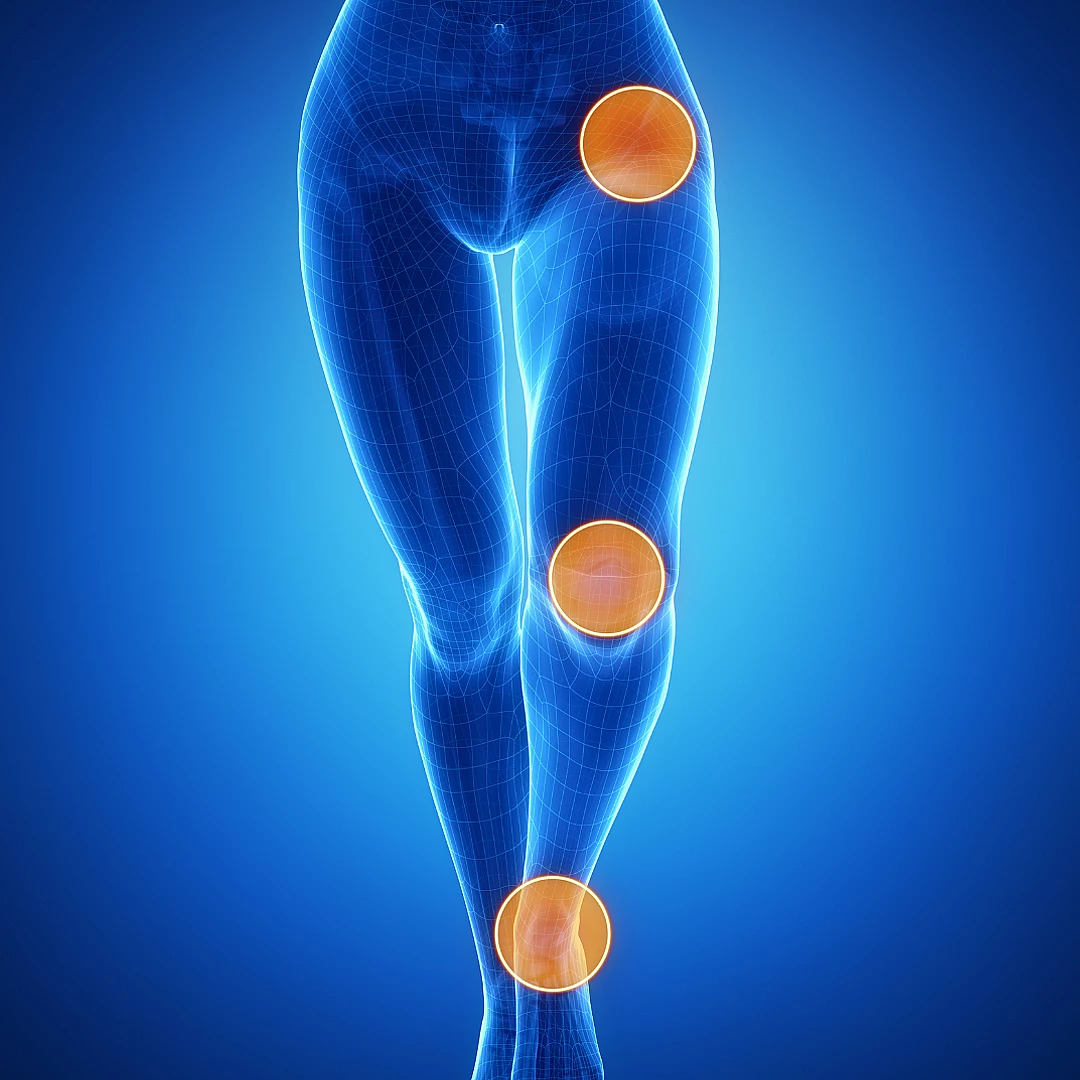

علاج خشونة الصابونة

أحد أمراض الركبة الشائعة التي تؤثر على جودة حياة المريض بسبب الألم المصاحب للحركة، خاصة أثناء المشي.

العوامل المساهمة في حدوث خشونة الصابونة:

• الإصابات القديمة

• التحميل الشديد في بعض النشاطات الرياضية

• تقدم العمر

• زيادة الوزن

المشاكل المصاحبة: ضعف في عضلات الفخذ الأمامية مما يزيد من الإحساس بالألم وعدم الثبات

العلاجات التحفظية هي الأدوية، العلاج الطبيعي، بعض الحقن مثل البلازما، تقوية العضلات كركيزة أساسية للعلاج، أما الجراحة تكون للحالات التي لم تستجب للعلاج التحفظي أو الحالات المتقدمة.